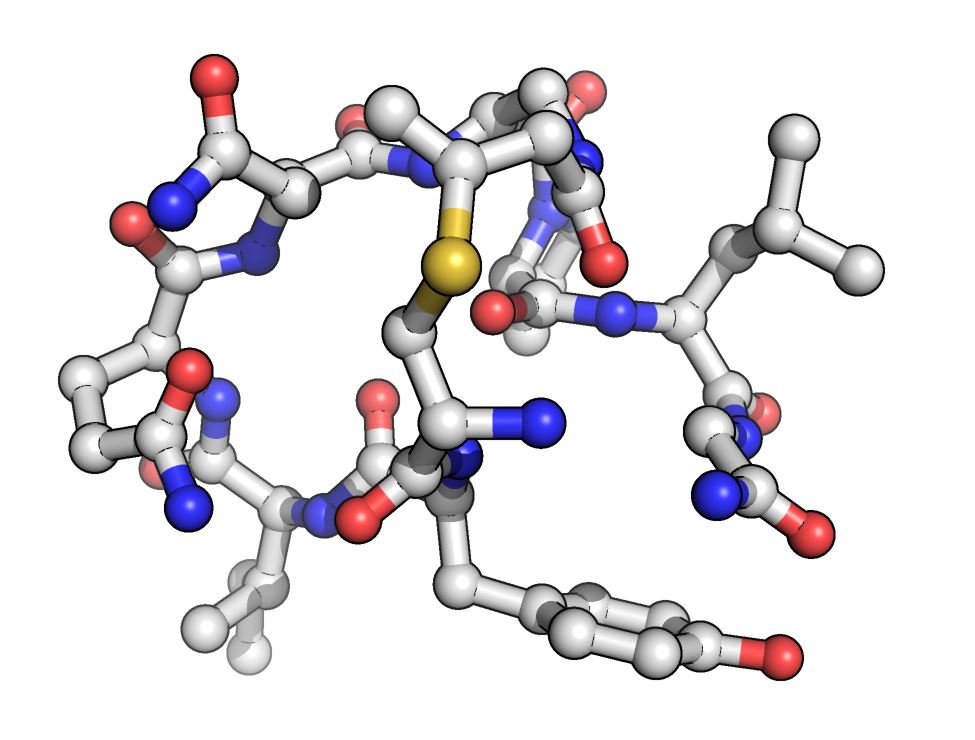

Exciting building blocks unlock peptide potential

Coined ‘bacterial super villains’, the World Health Organisation has a list of ‘priority pathogens’ which have developed resistance to most drugs. With the rise of these supe

read the full story

Building blocks for new medicines

The MWC uses New Zealand’s outstanding medicinal chemistry expertise to discover new medicines. A particular kind of chemistry that uses natural building blocks is now being used t

read the full story

Using 'molecular superglue' to build protein trees

Biological batteries, new vaccines and more cost-effective pharmaceuticals are just some of the potential benefits of Maurice Wilkins Centre research into the use of so-called mole

read the full story

The intriguing matter of cracking bacterial bonds (2014)

Maurice Wilkins Centre investigators at the University of Auckland are world leaders in discovery of new cross-links in proteins.

read the full story